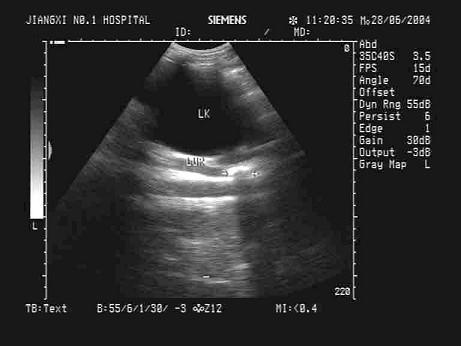

问题 某患者左腹部疼痛,根据左肾区超声声像图,最可能的诊断为?(?)

选项 A.左肾结石并左肾积水 B.左输尿管结石并左肾重度积水 C.左输尿管结石 D.左肾结石 E.左输尿管结石并左肾轻度积水

答案 B